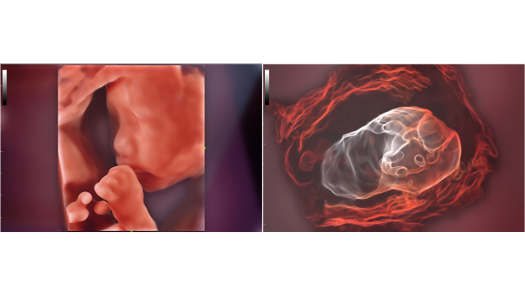

Dise?ado especĂficamente para usuarios de atenciĂłn primaria, el equipo Consona presenta soluciones nuevas y concretas que lo ayudan a realizar diagnĂłsticos sin problemas y de manera eficiente en diversos tipos de pacientes.

Independientemente de si lleva a cabo su rutina en hospitales o clĂnicas, o si estĂĄ perfeccionando sus habilidades en aplicaciones de diagnĂłstico por imĂĄgenes generales, atenciĂłn de la salud de la mujer o especialidades cardiovasculares, esta serie dispone de herramientas muy potentes para que se mantenga a la vanguardia.

GalerĂa de imĂĄgenes